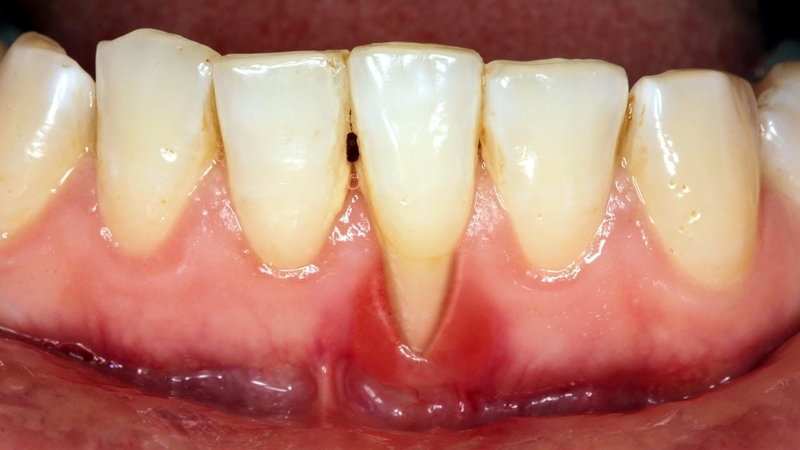

Tụt lợi là tình trạng lợi bị tụt về chân răng, lộ một phần mặt chân răng. Khi chân răng bị lộ, lớp men răng bên ngoài dễ bị mòn, gây ra cảm giác đau nhức, ê buốt, khó chịu khi ăn thực phẩm quá nóng, lạnh hoặc chua. Tình trạng này xảy ra ở một hoặc một vài răng, thậm chí là cả hàm răng. Có nhiều nguyên nhân gây ra tình trạng tụt lợi và nó phát triển qua nhiều giai đoạn. Ở giai đoạn đầu, triệu chứng thường không rõ ràng, dễ bị bỏ qua mà không được can thiệp, điều trị kịp thời.

Tụt lợi răng lung lay có 3 mức độ:

Người bị tụt lợi răng lung lay thường xuyên chảy máu chân răng, lợi sưng đỏ, răng nhạy cảm, ê buốt và khó chịu khi ăn uống. Điều này không chỉ ảnh hưởng nghiêm trọng đến sức khỏe răng miệng mà còn tác động tiêu cực đến sức khỏe toàn thân. Ăn uống trở nên không ngon miệng, gây chán ăn, cơ thể mệt mỏi, uể oải và có nguy cơ thiếu dinh dưỡng, thiếu máu cao.